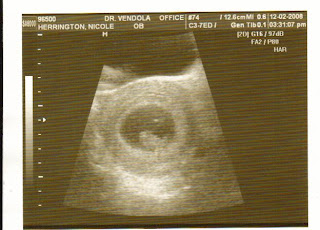

And here are a few pics from his labor and birth.